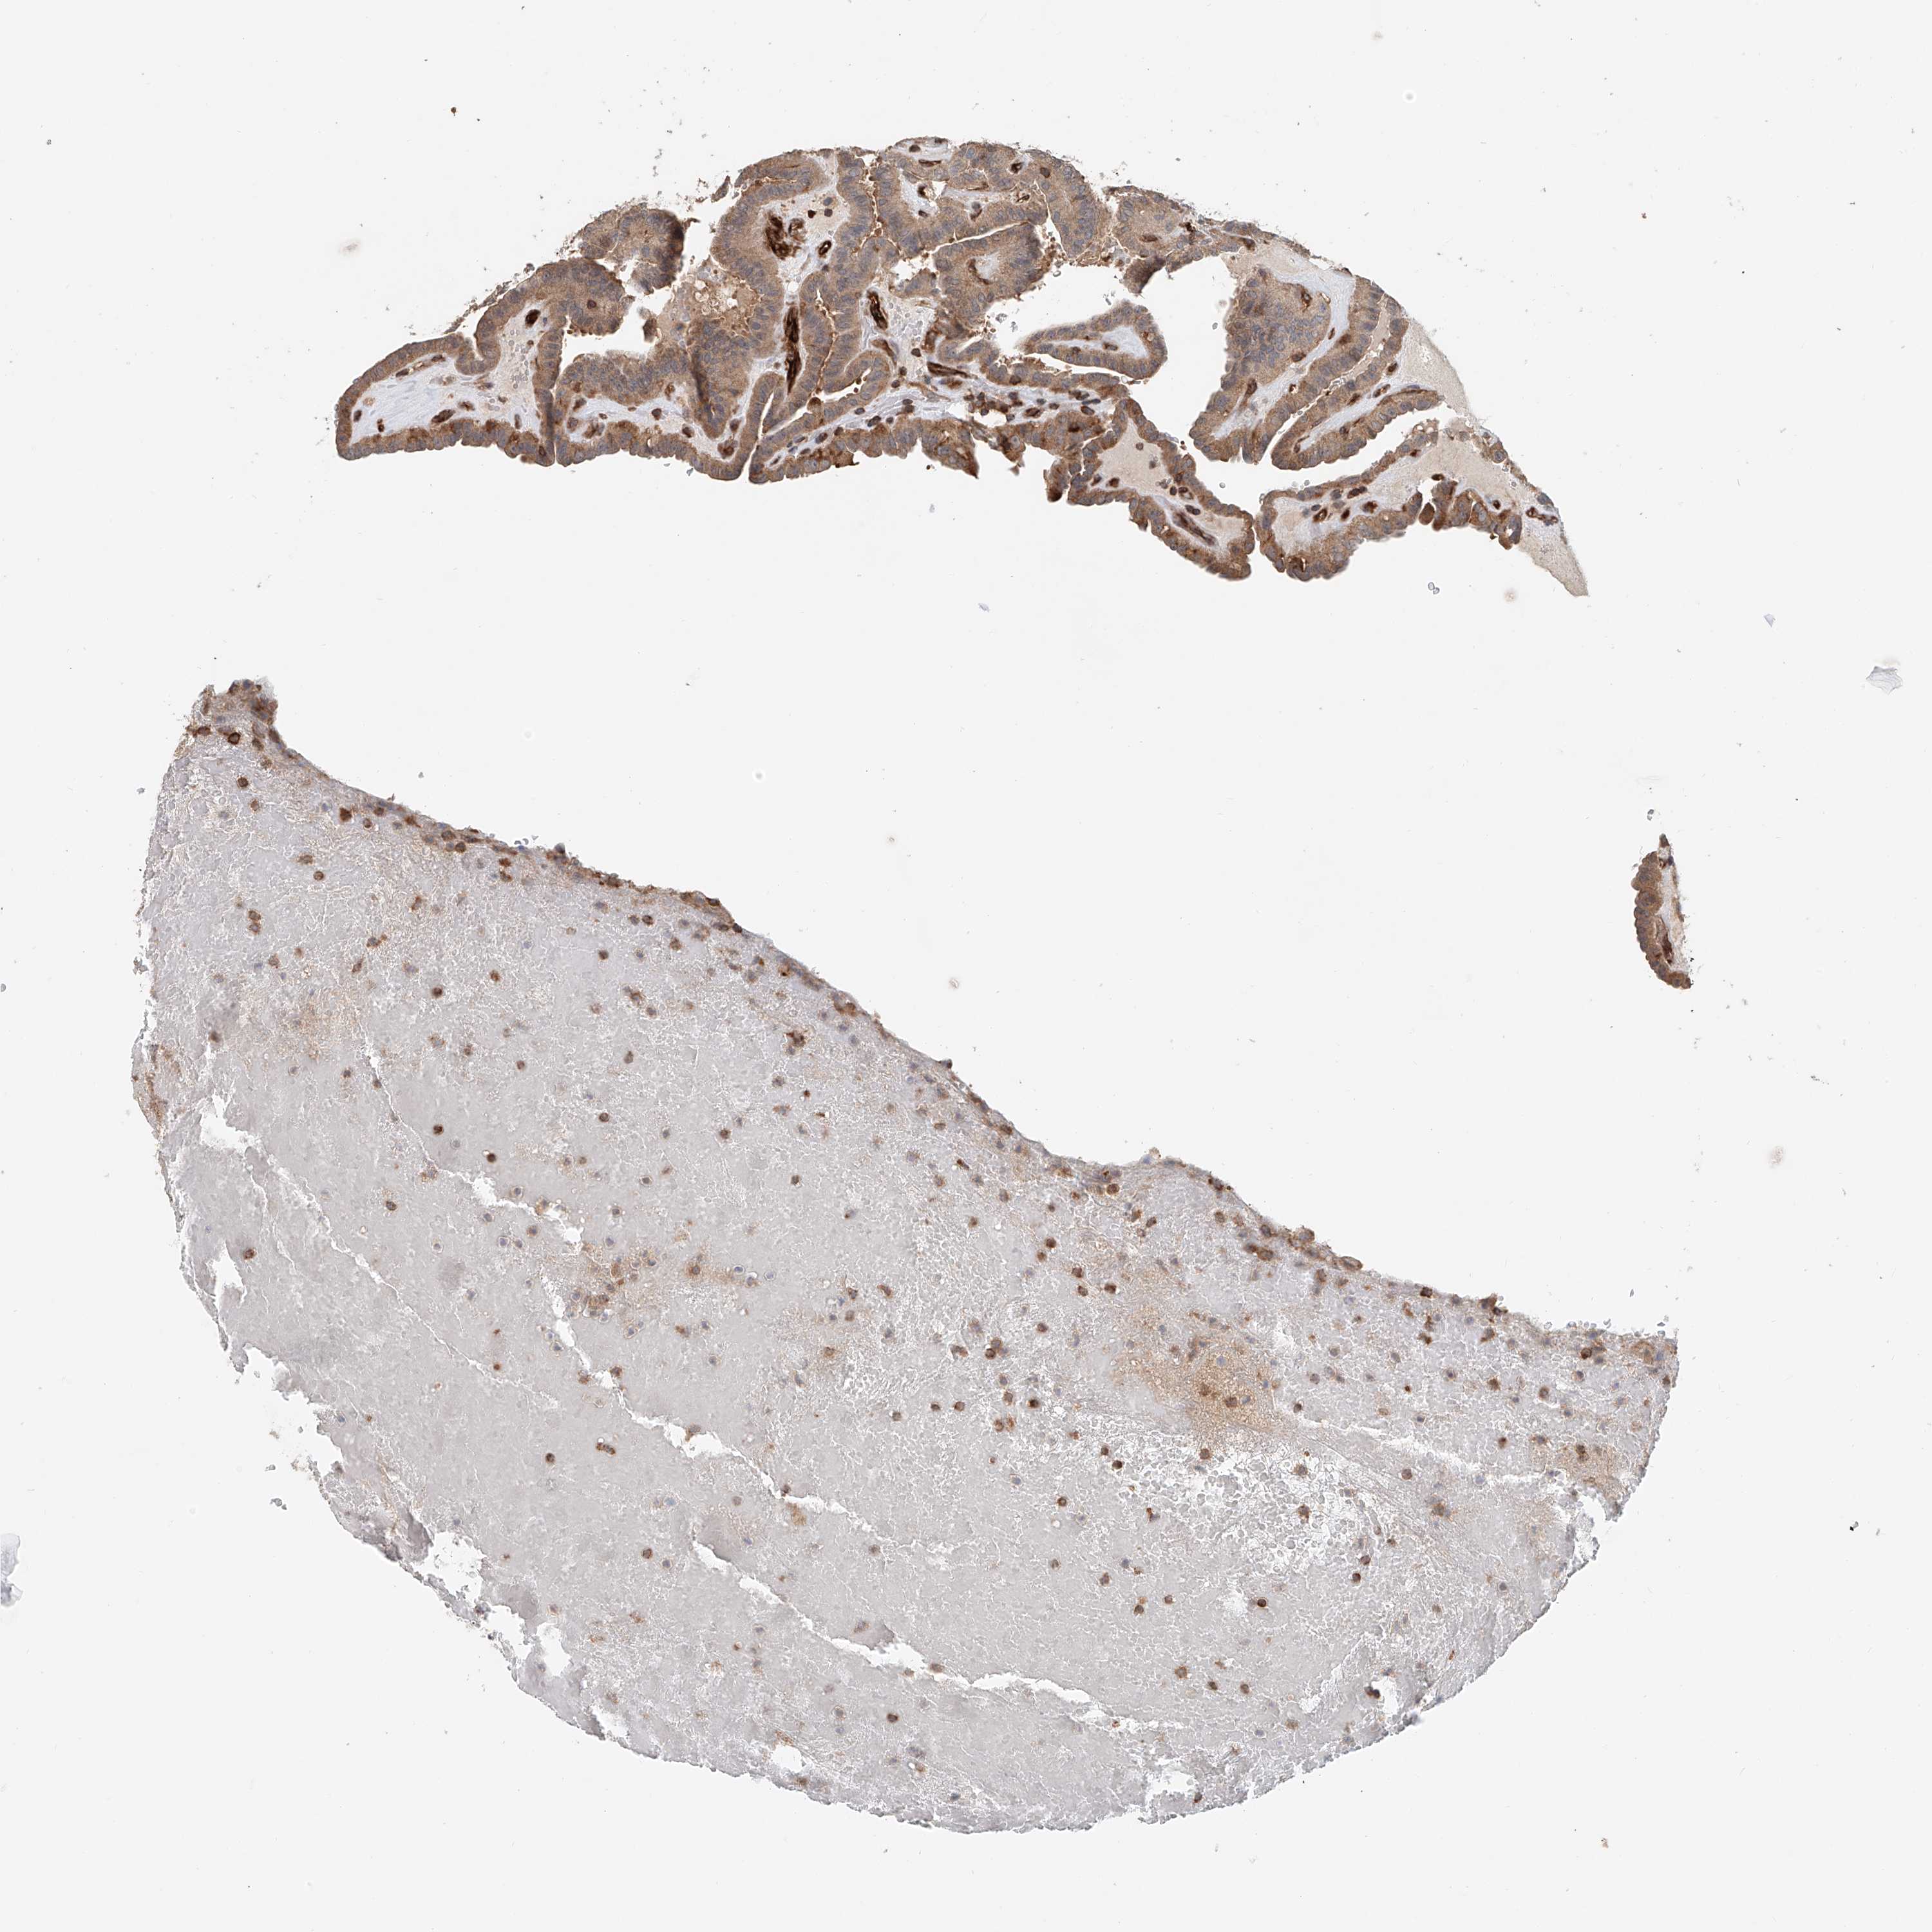

THYROID CANCER - Protein expressioni

A mouse-over function shows sample information and annotation data. Click on an image to view it in a full screen mode. Samples can be filtered based on level of antibody staining by selecting one or several of the following categories: high, medium, low and not detected. The assay and annotation is described here.

Note that samples used for immunohistochemistry by the Human Protein Atlas do not correspond to samples in the TCGA dataset.

Antibody stainingi

Antibody staining in the annotated cell types in the current human tissue is reported as not detected, low, medium, or high, based on conventional immunohistochemistry profiling in selected tissues. This score is based on the combination of the staining intensity and fraction of stained cells.

Each image is clickable and will lead to virtual microscopy that enables deeper exploration of all samples and also displays staining intensity scores, fraction scores and subcellular localization as well as patient and tissue information for each sample.

Antibody HPA031106

Antibody HPA031107

Staining

High

Medium

Low

Not detected

Intensity

Strong

Moderate

Weak

Negative

Quantity

>75%

75%-25%

<25%

None

Location

Nuclear

Cytoplasmic/membranous

Cytoplasmic/membranous,nuclear

Papillary adenocarcinoma, NOS

Follicular adenoma carcinoma, NOS